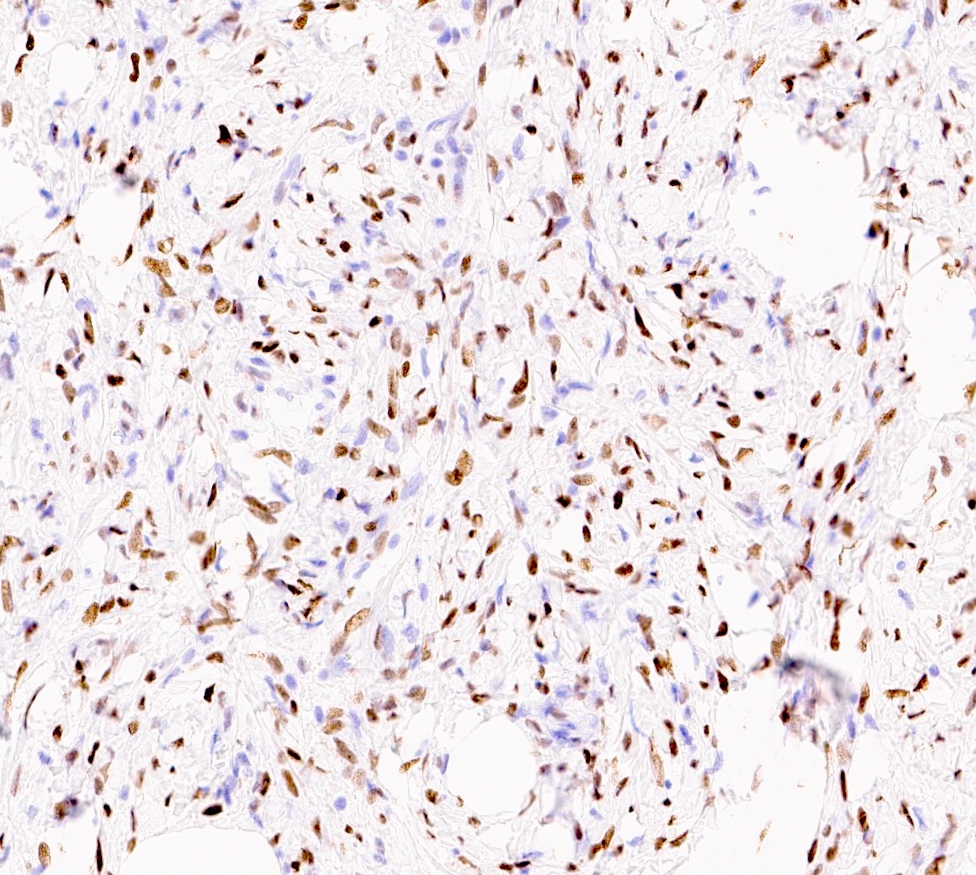

Microscopic (histologic) images

Positive stains

- Desmin (91%), vimentin, ER, PR, AR, BCL2, CD10, CD99 (Histopathology 2000;36:515, Virchows Arch 2007;450:727)

- CD34 (89%) diffuse and strong characteristic but may uncommonly show absent / focal expression (Am J Surg Pathol 2016;40:361, Breast J 2018;24:55)

- H-caldesmon if smooth muscle differentiation / leiomyomatous variant (Hum Pathol 2016;58:54, Histopathology 2003;42:233)

Negative stains

- Rb (negative in 89 - 92%) (Am J Surg Pathol 2016;40:361, Am J Surg Pathol 2012;36:1119)

- Actin (negative in 63%)

- Cytokeratins, S100, p63